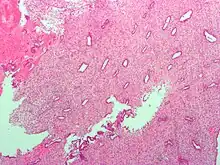

Histopathologic and cytopathologic images.

(A) proliferative endometrium (Left: HE × 400) and proliferative endometrial cells (Right: HE × 100)

(B) secretory endometrium (Left: HE × 10) and secretory endometrial cells (Right: HE × 10)

(C) atrophic endometrium (Left: HE × 10) and atrophic endometrial cells (Right: HE × 10)

(D) mixed endometrium (Left: HE × 10) and mixed endometrial cells (Right: HE × 10)

(E): endometrial atypical hyperplasia (Left: HE × 10) and endometrial atypical cells (Right: HE × 200)

(F) endometrial carcinoma (Left: HE × 400) and endometrial cancer cells (Right: HE × 400).